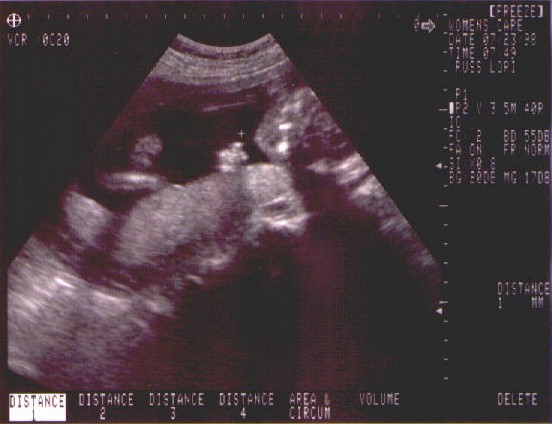

• 23rd July 1998 - Second and final ultrasound today (if nothing goes wrong).  We got to see a healthy developing baby girl.  Brain, heart, skeletal and organ development is on track and looking good.  We decide on the name for sweet pea - Caitlin Elizabeth Russ.  Take a look at the sonograms we have from the ultrasound.

You know it's my kid.  Here she is flipping off the entire world.  (I think she wanted us to get out until she got dressed.  I guess this is what I have to look forward to. ;-)